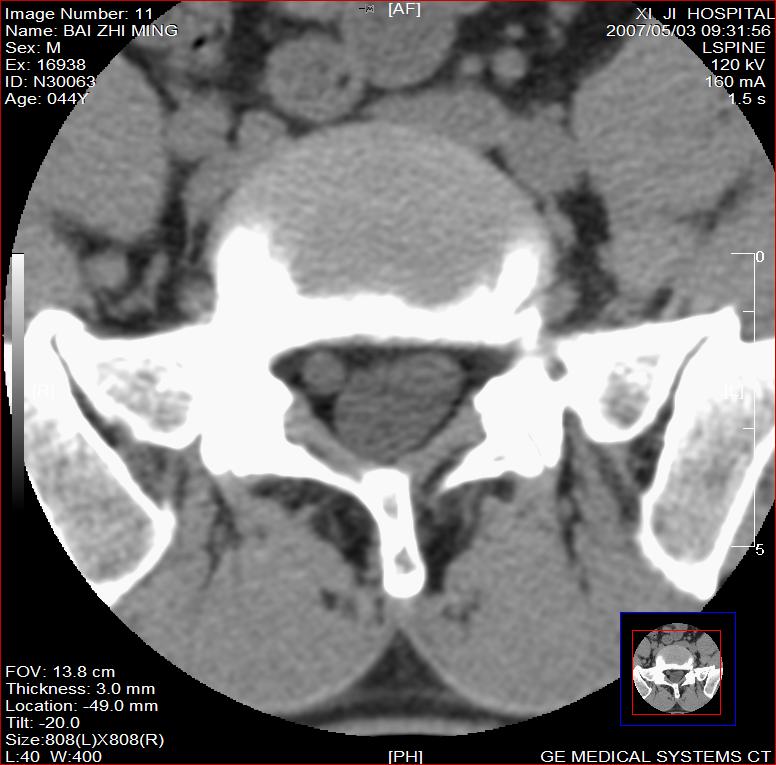

标题: CT8228:男,44岁,腰痛3月,加重3天,这是正常的吗?

男,44岁,腰痛3月,加重3天。

同意2楼,左侧神经根增粗,欠规整,神经根炎或神经源性肿瘤可能,建议mri检查。

左侧神经根增大.并硬脊膜囊受压(1,神经根炎2神经根肿瘤)

左侧神经根增粗,欠规整,神经根炎或神经源性肿瘤可能,建议mri检查